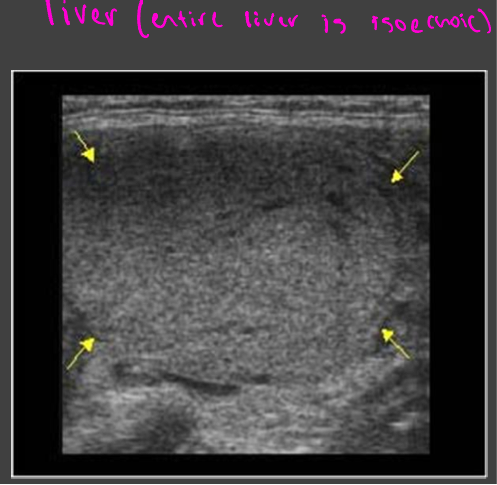

Echogenicity

Isoechoic

Uniform in color

Liver